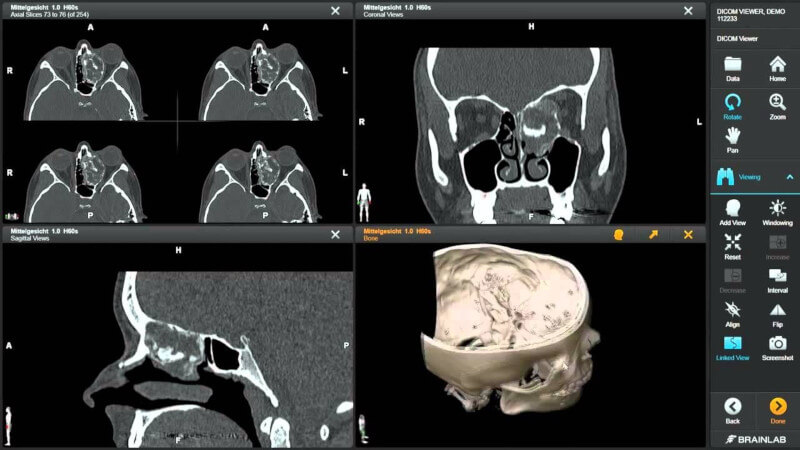

12. Inobitec DICOM Viewer

Inobitec DICOM Viewer is a specialized software tool designed for the visualization and analysis of medical images stored in the DICOMformat.

Inobitec’s viewer stands out for its user-friendly interface, allowing healthcare professionals to efficiently view, analyze, and interpret medical images. It supports a wide range of imaging modalities, such as MRI, CT, and X-ray.

With advanced features like 3D rendering, multiplanar reconstructions, and various measurement tools, the Inobitec DICOM Viewer aids in accurate diagnostics, making it a valuable asset for clinicians and radiologists.